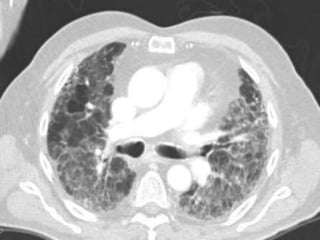

Septal Pattern – lymphatic/venous

● Smooth – pulmonary veno-occlusive disease, mitral

● Beaded – lymphangitic carcinomatosis, lymphoma,

PHTN – PA 39mm

PHTN and septal thickening

? PVOD